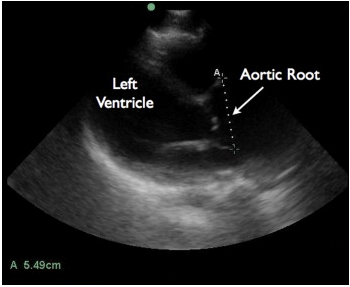

In a recent article in the Journal of Emergency Medicine, Dr. Resa Lewiss and friends, discuss 2 cases of thoracic aortic aneurysm identification by focused cardiac ultrasound. It is a great case report that highlights the need to include the aortic root and descending thoracic aorta in the parasternal long view of your focused cardiac echo.

“A 60-year-old man presented to the emergency department (ED) after a blunt traumatic injury to his back while at work. During the focused cardiac ultrasound examination, the aortic outflow tract distal to the aortic valve appeared enlarged and the aortic root measured 5.49 cm.

Screen Shot 2014-03-04 at 9.16.55 AM